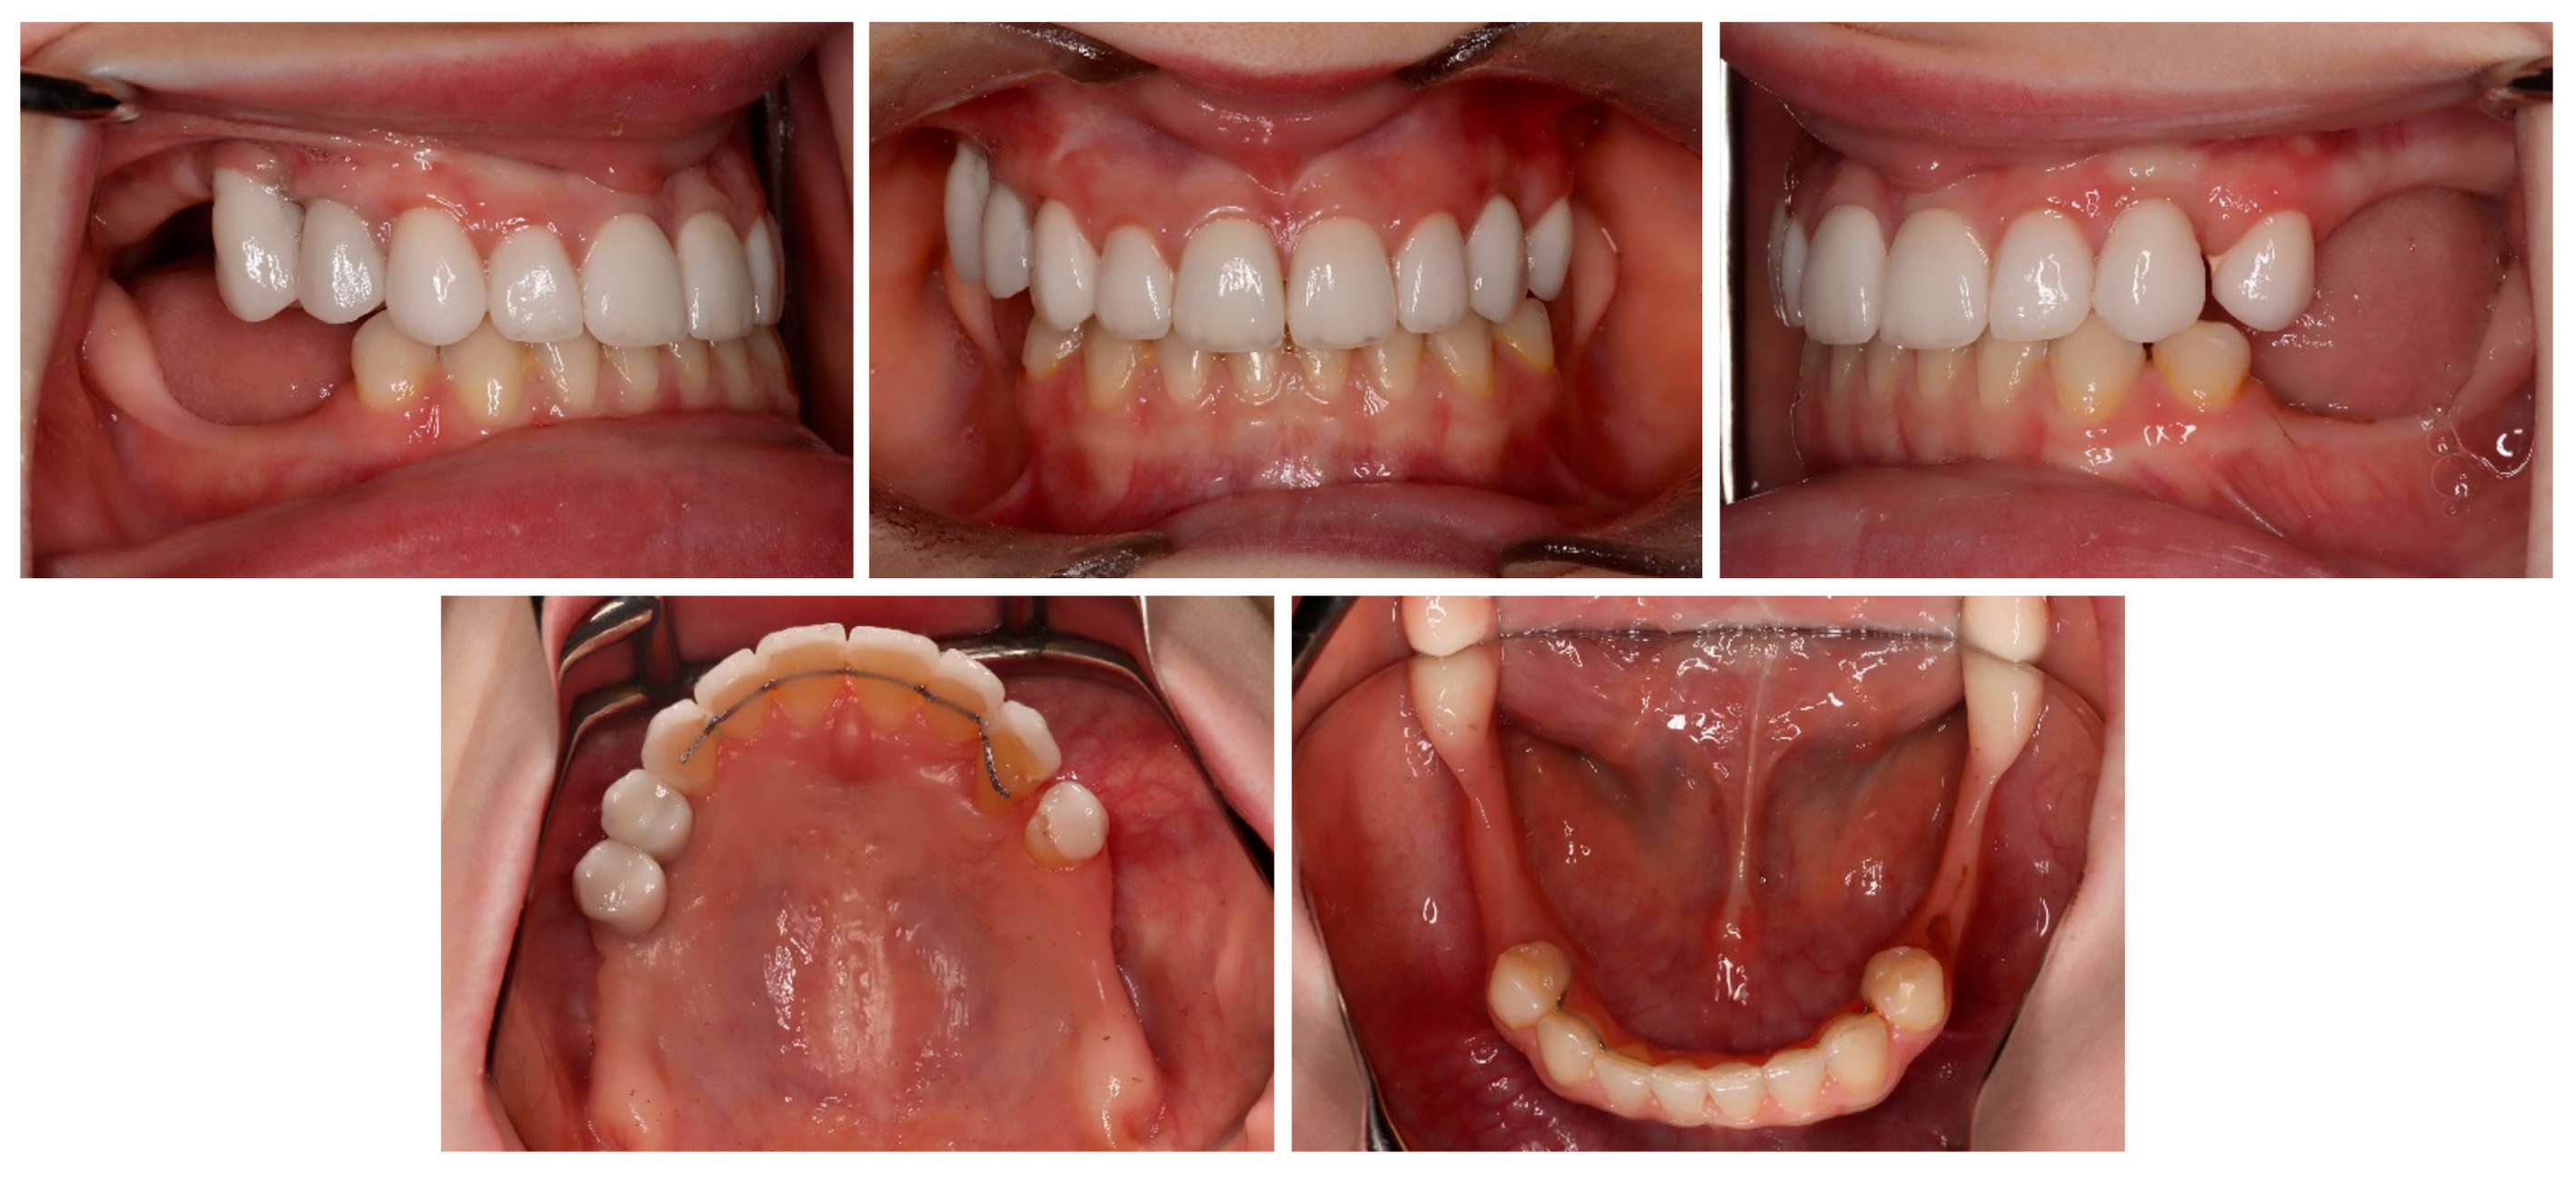

| May–August 2022 | Finishing; control panoramic X-ray (Figure 8); 1st canine relationships and midline consistency; debonding of the brackets; fixed upper and lower retainers’ placement (0.027″ × 0.011″ 8-strand braided SS), tooth no. 24 was not fixed to the retainer due to increased mobility. |

| September 2022 | E-max (lithium desilicated ceramic) veneers on upper teeth; individual implant abutments (titanium pre-milled abutments) and implant-supported blocked crowns (zirconia veneered with porcelain using the cut-back technique) on dental implants; removable thermoformable retainer. |

| March 2023 | Retention phase: 10-month follow-up. Stability of treatment results; minimal opening of the spaces mesially to teeth no. 34 and 44; proper mobility of tooth no. 24. Bleaching of the lower teeth. |